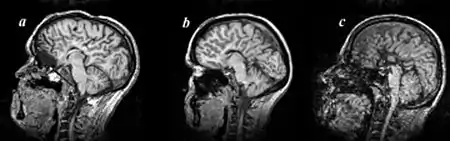

Colpocephaly is characterized by disproportionately large occipital horns of the lateral ventricles (also frontal and temporal ventricles in some cases). MRI and CT scans of patients demonstrate abnormally thick gray matter with thin poorly myelinated white matter. This happens as a result of partial or complete absence of the corpus callosum. Corpus callosum is the band of white matter connecting the two cerebral hemispheres. The corpus callosum plays an extremely important role in interhemispheric communication, thus lack of or absence of these neural fibers results in a number of disabilities.[12]

After birth, MR imaging can be done to look for cephalic abnormalities. This is the most commonly used method for diagnosing colpocephaly. Physicians look for abnormally large occipital horns of the lateral ventricles and diminished thickness of white matter.[12] Spinal tapping is not a preferred method for diagnosis because newborn babies with colpocephaly or hydrocephaly have open fontanelles which makes it difficult to collect CSF. Also, colpocephaly is not associated with increased pressure.[13]